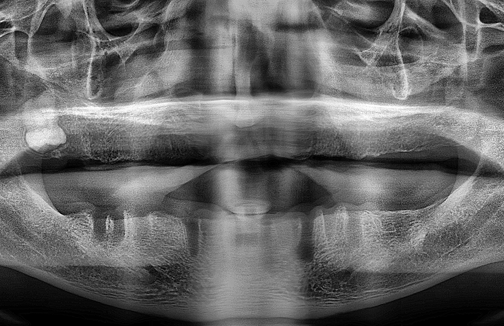

연세준치과는 숙련된 의료진의 경험과 첨단 디지털 장비로

데이터 기반의 과학적인 분석과 예측을 통해

더욱 빠르고 정확한 결과를 제공합니다.